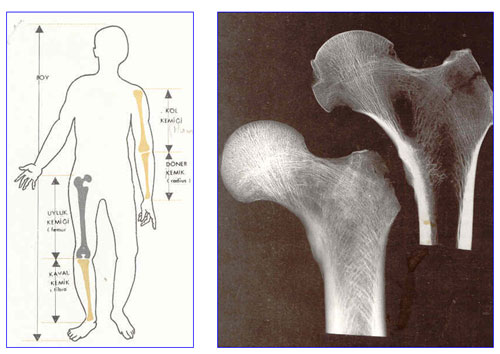

Uyluk kemiğinin (femur) insan vücudundaki yeri. Rontgen filminde femur kemiğinin kenar bölgelerin sertliği, iç kısmın boşluğu açıkça görülüyor.

Şayet insanda kemiklerin içleri boş değil de, bakır tel veya demir çubuk gibi, yekpare kemik dokusu ile dolu olsa idi, acaba iskelet daha sağlam olmaz mı idi sorusu hatırımıza gelebilir. Şöyle bir araştırma yapılmış; Aynı miktar malzeme kullanarak, bir demir çubuktan, su boruları şeklinde profil yani içi boş boru yapılmış. Su borusu şeklindeki borunun, aynı miktar malzemeyi taşıyan içi dolu demir çubuğa göre beş misli daha sağlam olduğu görülmüştür. İşte bedenimizde, bilhassa uzun kemiklerde kemiklerin yaratılışında aynı metot tatbik edilmiştir. Bir anatomi kitabından bu mevzu ile alakalı pasajı aynen aktarıyorum; “İnsan kemiğinde az madde sarfiyatı ile kemiğin daha fazla dayanıklı olması mümkün olmuştur. Uyluk kemiğini (femur) misâl verecek olursak, bu kemik tamamen dolu, yekpare solid bir kemik dokusundan yapılmış olsa idi, içi boş olmasa idi, sağlamlık ve dayanıklık açısından fazla bir şey kazanmazdık. Fakat fazlaca madde sarfiyatı bakımından ve birde kemiğin ağırlığının artması yönünden, lüzumsuz yere kilolarca fazlalığı taşımak bakımından çok şey kaybetmiş olurduk.” (Odar I V : Anatomi Ders Kitabı. I.cilt, 12. baskı, Elif Matbaacılık, 1978, Ankara, sh.20.)

Cenab-ı Hak eşyayı yaratırken, bu misâldeki gibi, en hafif sureti, en kısa yolu, en kolay tarzı, en faideli şekli ehemmiyetle takip etmiştir. Buna insan bedeninden bir örnek verelim. Bilineceği gibi insan bedenini zahirde ayakta tutan, akciğer, karaciğer gibi narin, hassas organları koruyan iskeletin büyük ekseriyeti, sertliği ile bildiğimiz kemik dokusudur. Kemik dokuları genel yapısı itibarı ile, bir tel, bir demir çubuk gibi içleri dolu değil, bir su borusu veya bir profil boru gibi içleri boştur. Daha doğrusu kemiklerin içleri, kemik iliği diye bildiğimiz, kan hücrelerinin yaratıldığı bir hafif doku ile doldurulmuştur.